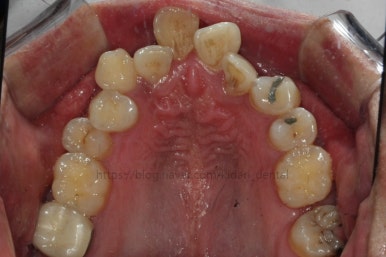

치료 1년 째의 모습입니다.

앞선 모습과 큰 차이가 없는 듯 하죠?

다른 치아는 어떻게 보면 움직임을 멈춘 상태입니다. 오로지 치료는 화살표 치아를 움직이는데 온 힘을 쏟는 중이에요. 이 치아가 제 위치를 잡아야 남아 있는 틈을 모으든 교합을 맞추든 다음 진도를 나갈 수 있기 때문이지요.

치료 1년 5개월째의 모습입니다.

작은 어금니가 어느 정도 올라왔다고 판단되어, 본격적으로 틈을 줄이기 시작했어요.

오른쪽 아래 맨 뒤어금니는 예후가 불량하여 살려쓰기 힘들다고 판단이 되어 발치했어요. 추후에 임플란트를 하셔야 합니다.